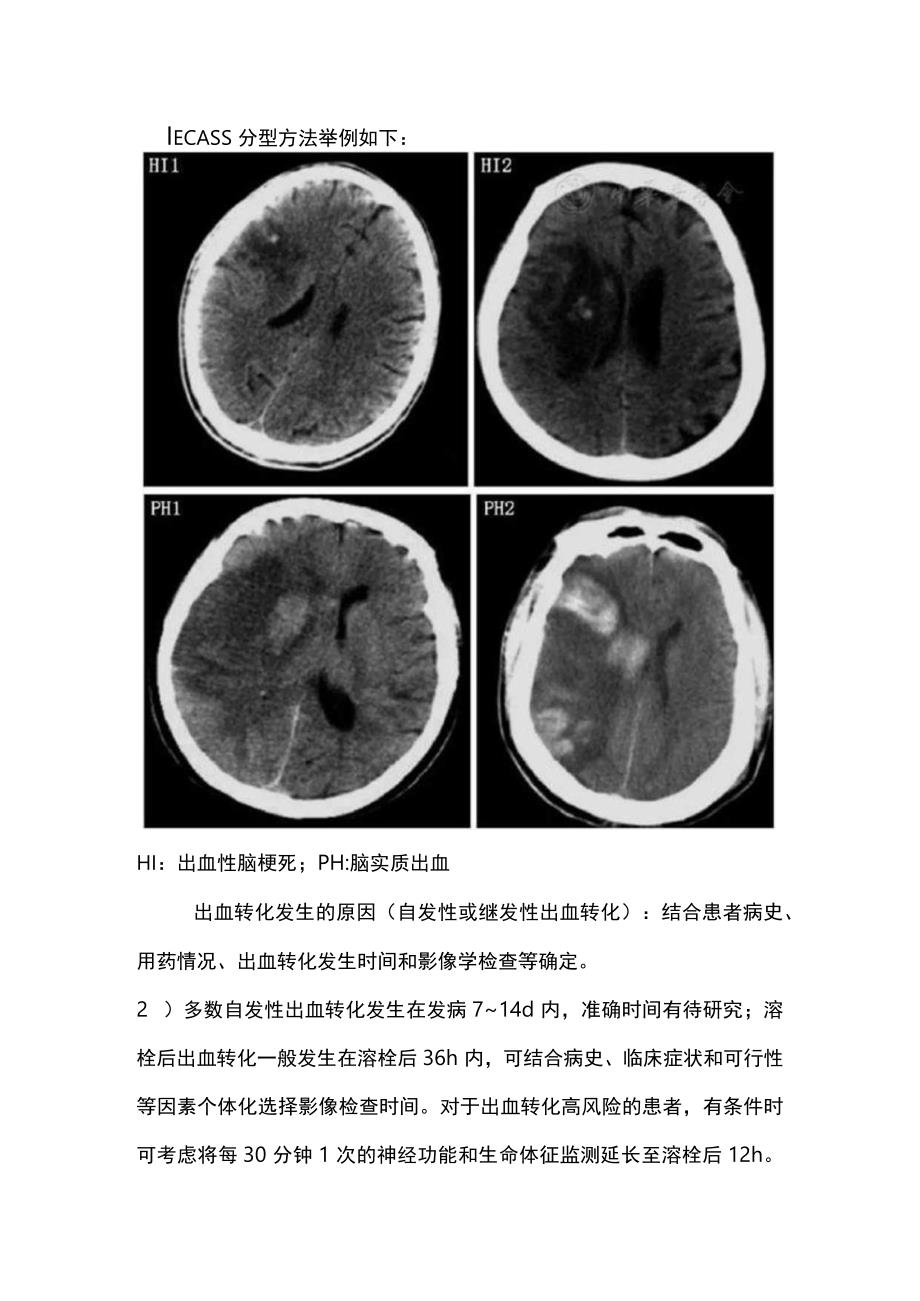

2、他公认标准评估患者临床症状是否加重,考虑是否为症状性出血转化。出血转化影像分型:可采用ECASS分型或Heidelberg分型(表Iecass分型方法举例如下:hi:出血性脑梗死;PH:脑实质出血出血转化发生的原因(自发性或继发性出血转化):结合患者病史、用药情况、出血转化发生时间和影像学检查等确定。2 )多数自发性出血转化发生在发病714d内,准确时间有待研究;溶栓后出血转化一般发生在溶栓后36h内,可结合病史、临床症状和可行性等因素个体化选择影像检查时间。对于出血转化高风险的患者,有条件时可考虑将每30分钟1次的神经功能和生命体征监测延长至溶栓后12h。3)对于重症脑梗死患者(如NIHSS